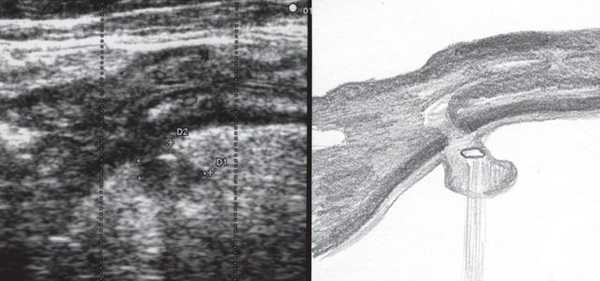

При УЗИ были выявлены диффузные изменения печени и поджелудочной железы, признаки хронического бескаменного холецистита, ангиомиолипома левой почки (без динамики за несколько лет), состояние после экстирпации матки с придатками. В левой подвздошной области соответственно зоне максимальной пальпаторной болезненности на протяжении 9 см отмечалось утолщение стенок толстой кишки до 6-7 мм (рис. 1). Перистальтика кишки отсутствовала, гаустрация была слабо выражена, при этом визуализировалось несколько болезненных при надавливании датчиком выпячиваний пониженной эхогенности, размером от 7 до 20 мм (рис. 2, а, б) с тонкой стенкой до 0,9-1,1 мм и наличием в некоторых из них фрагментов кишечного содержимого и газа (рис. 3, а, б).

Рис. 3. Эхографическая картина дивертикулита. Трансабдоминальное исследование конвексным датчиком 3,5 МГц.

В приведенном наблюдении при УЗИ визуализировались множественные выпячивания истонченной кишечной стенки. На участках утолщенной стенки между дивертикулами и в самих дивертикулах сосудистый рисунок был обеднен или не визуализировался, что подтверждает роль сосудистого фактора в развитии болезни: сдавление внутристеночных сосудов с нарушением микроциркуляции, наличие ишемии и замедления венозного оттока. Некоторые дивертикулы были заполнены гомогенным аваскулярным содержимым средней эхогенности, без признаков внутрипросветного движения, так что содержимое сливалось с изображением стенки. В других дивертикулах пузырьки газа, выступая в качестве естественного контраста, позволили детально рассмотреть истонченную до 0,9-1,1 мм стенку кишки, лишенную гипоэхогенного мышечного слоя. Форма этих дивертикулов приближалась к шаровидной, устье было меньше, чем диаметр дивертикула. Однако встречались и выпячивания в форме конусов, с устьями, превышающими размеры самого дивертикула, в них прослеживалось продолжение гипоэхогенного мышечного слоя стенки.

Очевидно, эта разница в ультразвуковом изображении дивертикулов отражает стадии их формирования: округлые с истонченной стенкой и отсутствием в ней мышечного слоя - это сформированные дивертикулы, в то время как другие, в которых еще прослеживается мышечный слой или его фрагменты, - дивертикулы на стадии формирования.

Таким образом, газ в кишке может быть не только препятствием к адекватной визуализации, но и, являясь естественным контрастным средством, существенно обогащает ультразвуковую картину.